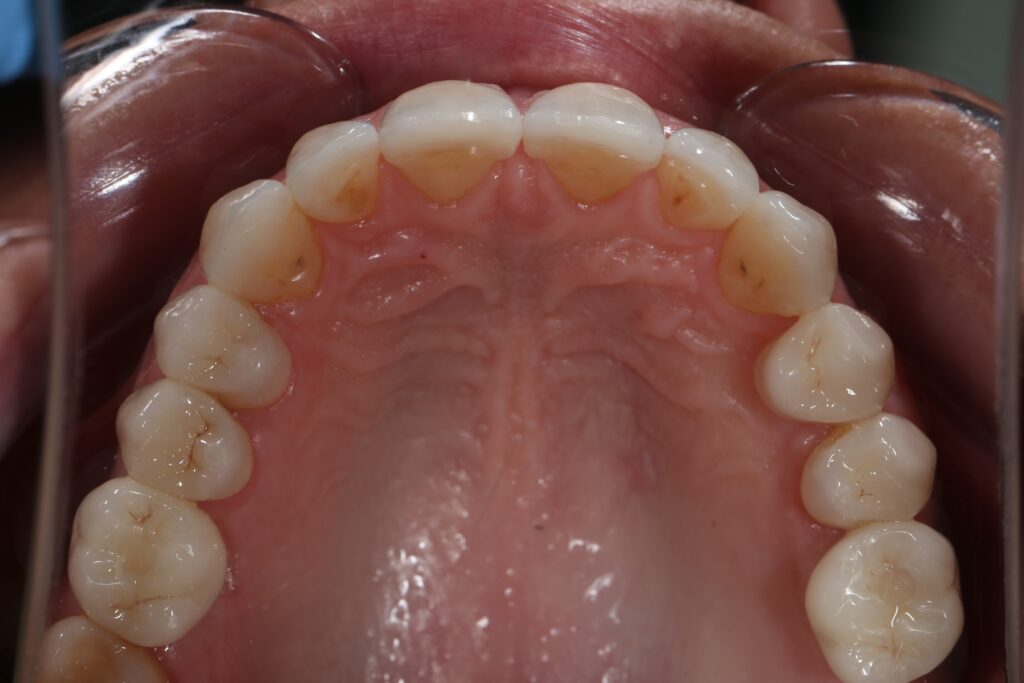

Этап имплантации и протезирования и результаты

Затем были установлены имплантаты Megagen AnyOne.

Спустя 3 месяца после установки имплантатов была произведена замена несостоятельных реставраций и пломб для избежания развития вторичного кариеса под винирами и коронками.

Сделано препарирование зубов на верхней и нижней челюстях с контролем глубины (0.7-0.8 мм) под керамические реставрации. Сняты оттиски с имплантатов.

Установлены временные виниры и коронки из пластика. Спустя 26 дней были зафиксированы керамические виниры и коронки на своих зубах и циркониевые коронки на имплантатах.